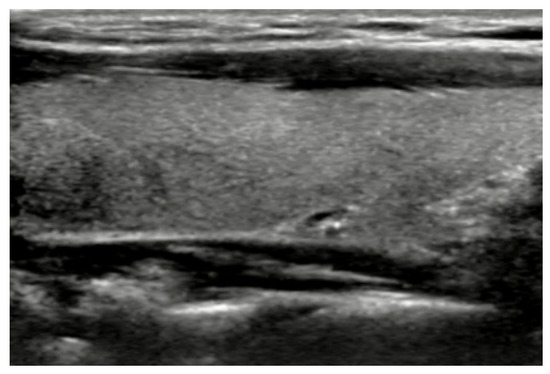

A longitudinal B-mode image of the normal thyroid was shown in Figure 1 where homogeneous isoechoic structure and nearly regular well-defined margins could be found in the image. Based on the echogenicity change in B-mode ultrasonography, the pathological change of thyroid gland was determined in clinics. Moreover, thyroid nodules could be classified by boundaries of ROI and texture features in images. Figure 2 shows distinct ultrasound features and accordingly pathologic findings comparing between benign and malignant lesions. A thyroid adenoma (Figure 2a) with ultrasonographic features of hyperechoic echogenicity, no calcification, and wider shape, was benign, finally proven by FNA findings. Its pathologic result showed that the follicular cavity is filled with gelatinous material, and that a papillary structure is partially visible (Figure 2c). On the contrary, hypoechoic echogenicity, microcalcification, and taller shape demonstrated a malignant papillary thyroid carcinoma (Figure 2b), with complex branched papillaries containing fibrous vascular cores (Figure 2d).

Figure 2.

B-mode US images and corresponding FNAs of benign and malignant thyroid nodules: (a) B-mode image of benign thyroid nodule; (b) B-mode image of malignant thyroid nodule; (c) FNA smears of benign thyroid nodule; and (d) FNA smears of malignant thyroid nodule.